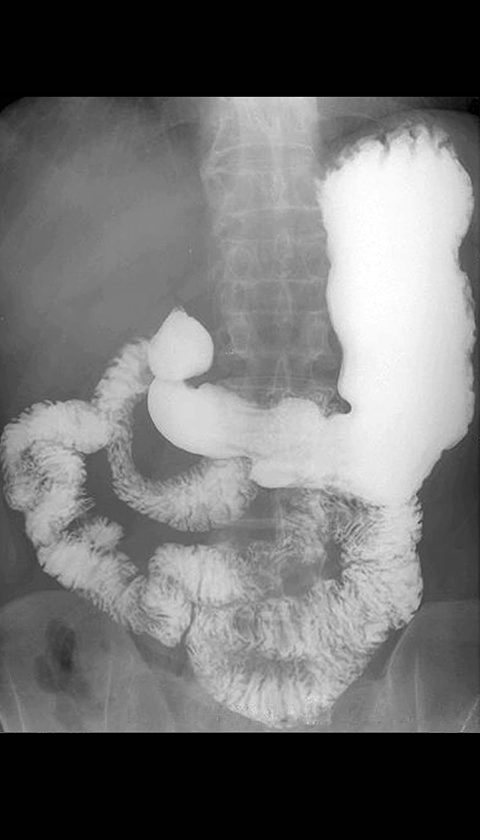

Barium Upper GI Study, normal stomach